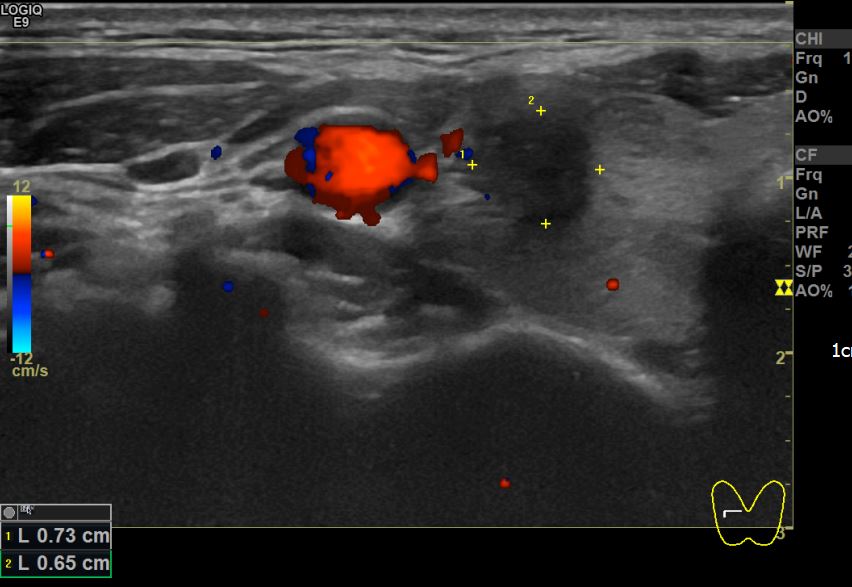

상기환자 타병원검진이후 결절있어 추적검사차 내원하신 40대초반 여성분으로 우엽 의심스러운혹 세포검사진행후 갑상선암으로 진단되었습니다